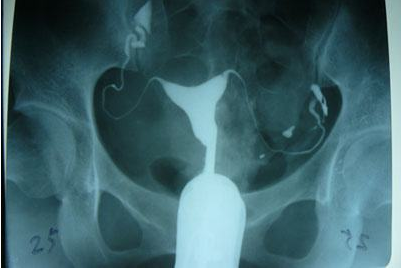

輸卵管造影是用來檢查女性輸卵管通暢與否的一種檢測方法。目前,輸卵管造影是臨床上應用較為廣泛的方法之一。造影是通過導管經陰道、宮頸、子宮腔直接插向子宮角的輸卵管開口處,對著輸卵管推注造影劑而使輸卵管顯影,進而了解輸卵管是否通暢、阻塞部位及宮腔形態的一種檢查方法。

推注造影劑力,造影劑進入盆腔緩慢,在停注造影劑數十分鐘后,可見造影劑在盆腔內彌散,但彌散欠佳。

輸卵管完全不顯影或顯影一段后不再顯影,且造影劑注入到一定劑量時阻力加大,盆腔內無造影劑影彌散。

造影劑積聚在輸卵管內,輸卵管常擴張呈囊狀或臘腸狀,以遠端明顯,多伴有輸卵管傘端阻塞。盆腔內一般無造影劑影彌散。